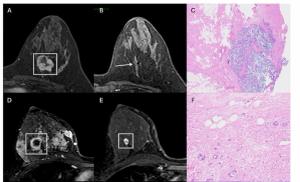

Employing a 77-second scan time for obtaining ultrafast breast MRI views, researchers found a 92.1 percent AUC for differentiating between benign and malignant lesions, according to new prospective study.